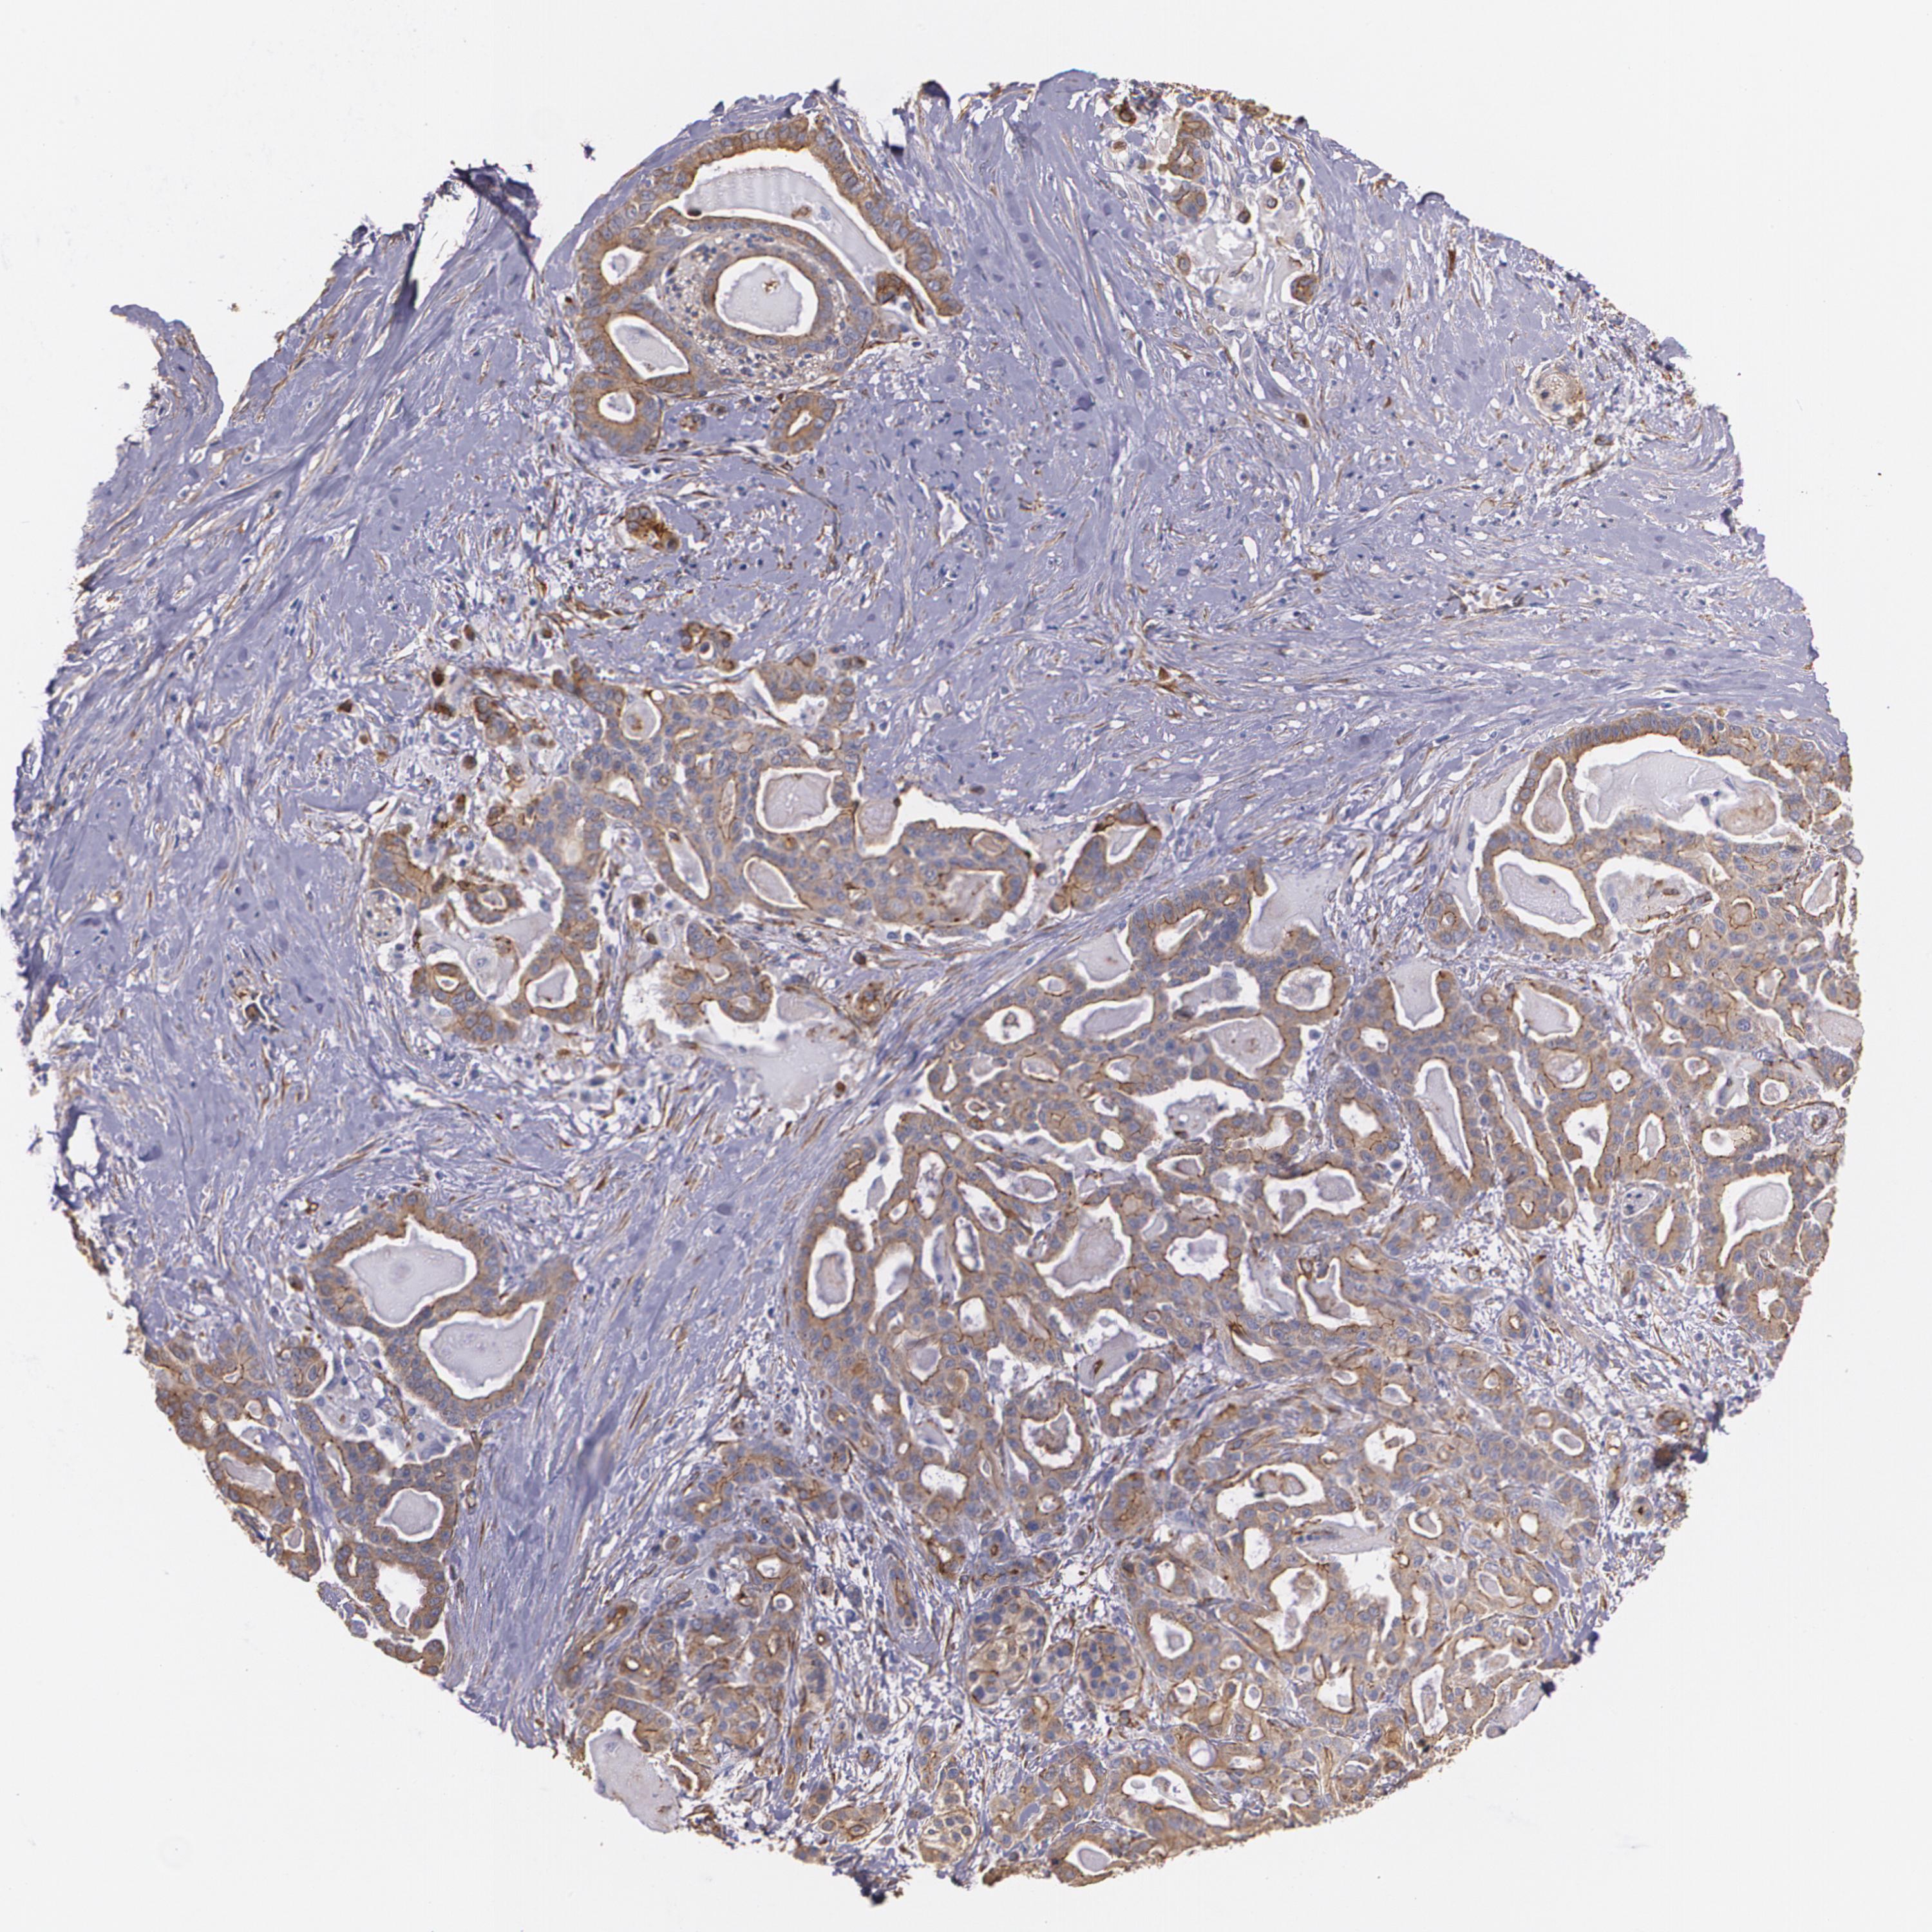

PANCREATIC CANCER - Protein expressioni

A mouse-over function shows sample information and annotation data. Click on an image to view it in a full screen mode. Samples can be filtered based on level of antibody staining by selecting one or several of the following categories: high, medium, low and not detected. The assay and annotation is described here.

Note that samples used for immunohistochemistry by the Human Protein Atlas do not correspond to samples in the TCGA dataset.

Antibody stainingi

Antibody staining in the annotated cell types in the current human tissue is reported as not detected, low, medium, or high, based on conventional immunohistochemistry profiling in selected tissues. This score is based on the combination of the staining intensity and fraction of stained cells.

Each image is clickable and will lead to virtual microscopy that enables deeper exploration of all samples and also displays staining intensity scores, fraction scores and subcellular localization as well as patient and tissue information for each sample.

Antibody HPA001636

Antibody HPA001637

Antibody CAB010822

Adenocarcinoma, NOS

Adenocarcinoma, metastatic, NOS